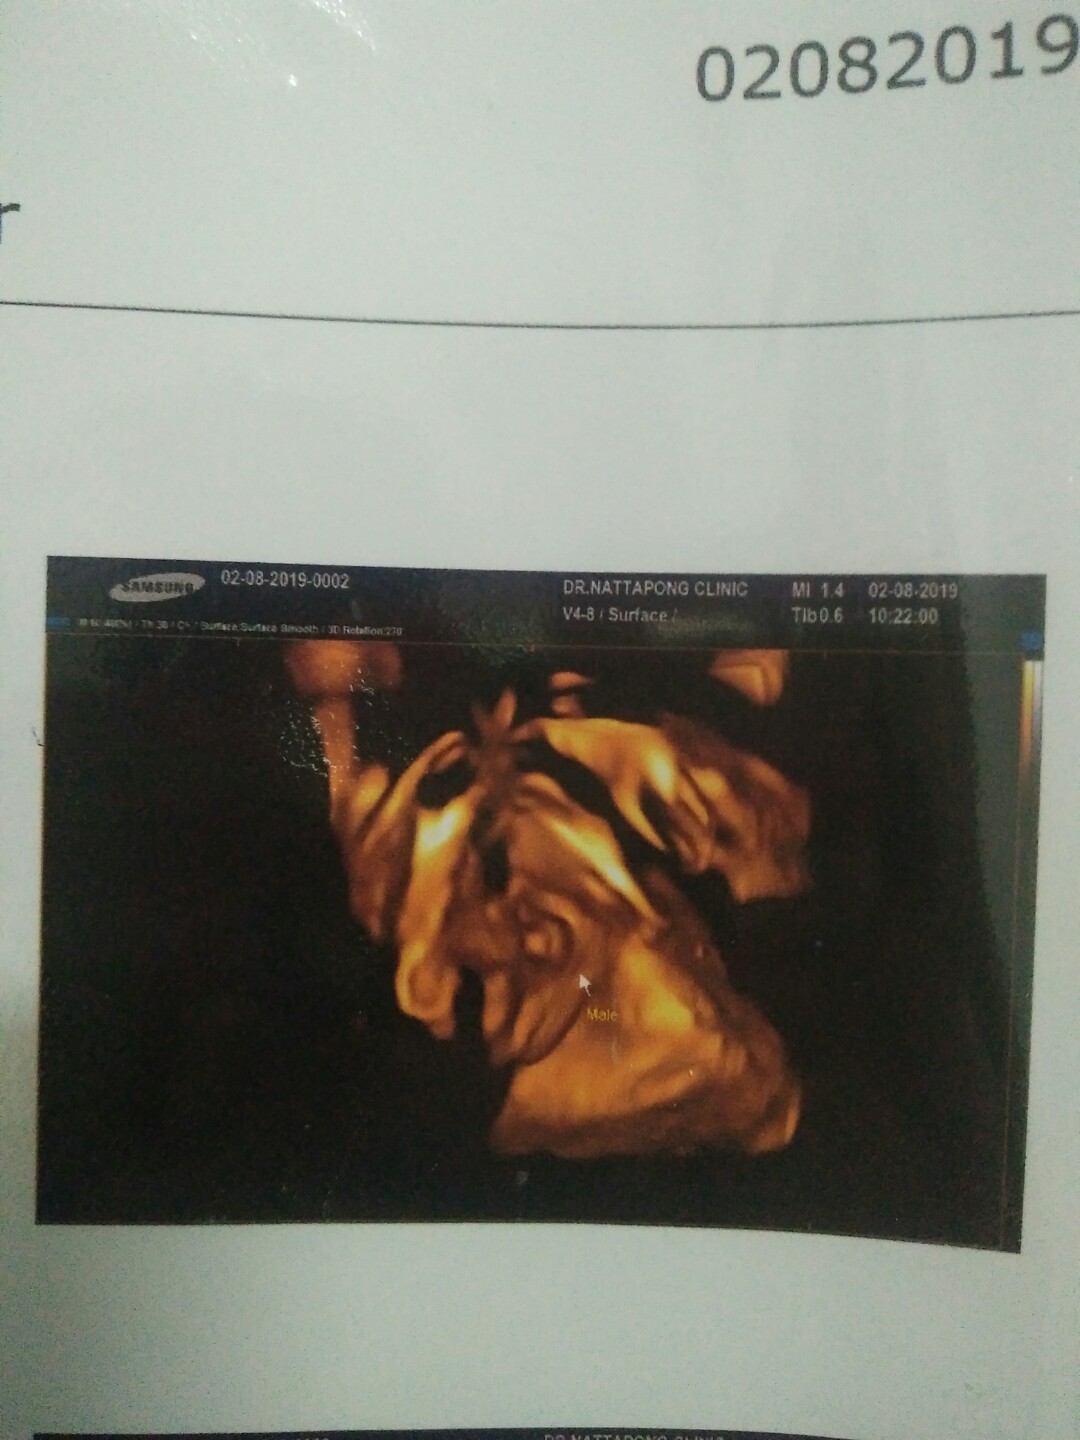

บ้านนี้มาเป็นแท่งเลยค่ะ 😄😊

ทั้งพวงทั้งแท่งเลยคร้าบ 😊😁

คุณหมอบอกผู้ชาย100%คร้าบบบ😂😂